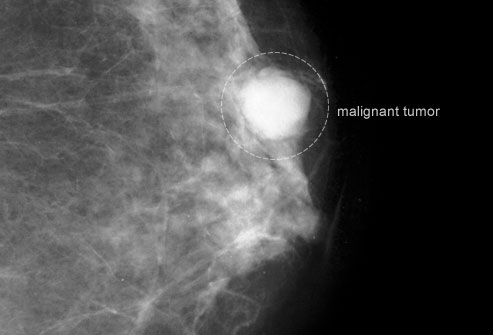

乳腺癌

乳腺癌发现得越早,治愈的几率越大。小尺寸的乳腺癌肿瘤不大容易扩散到淋巴结和重要器官,如肺和大脑。如果你的年龄处于二三十岁的阶段,你应该定期每三年进行一次乳腺检查。如果你有任何其他风险因素,你可能需要更频繁的检查。

乳腺钼靶筛查

乳腺钼靶是一种低剂量X光射线检查,虽然正常结果不能完全排除癌症可能,但是这种检查能够在你有感觉前发现肿块。当你的年龄处于四十多岁时,你应该每年进行一次乳腺钼靶检查。50至74岁之间时,每两年检查一次。当然,如果你属于高危人群,医生可能见你更频繁地接受检查。